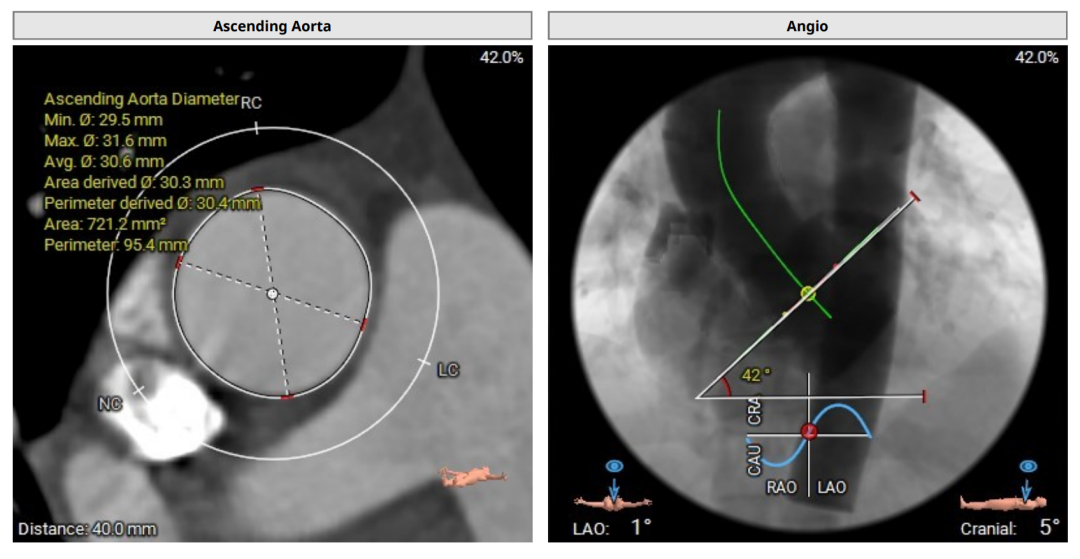

术前评估

术前CT(上下滑动查看更多图片)